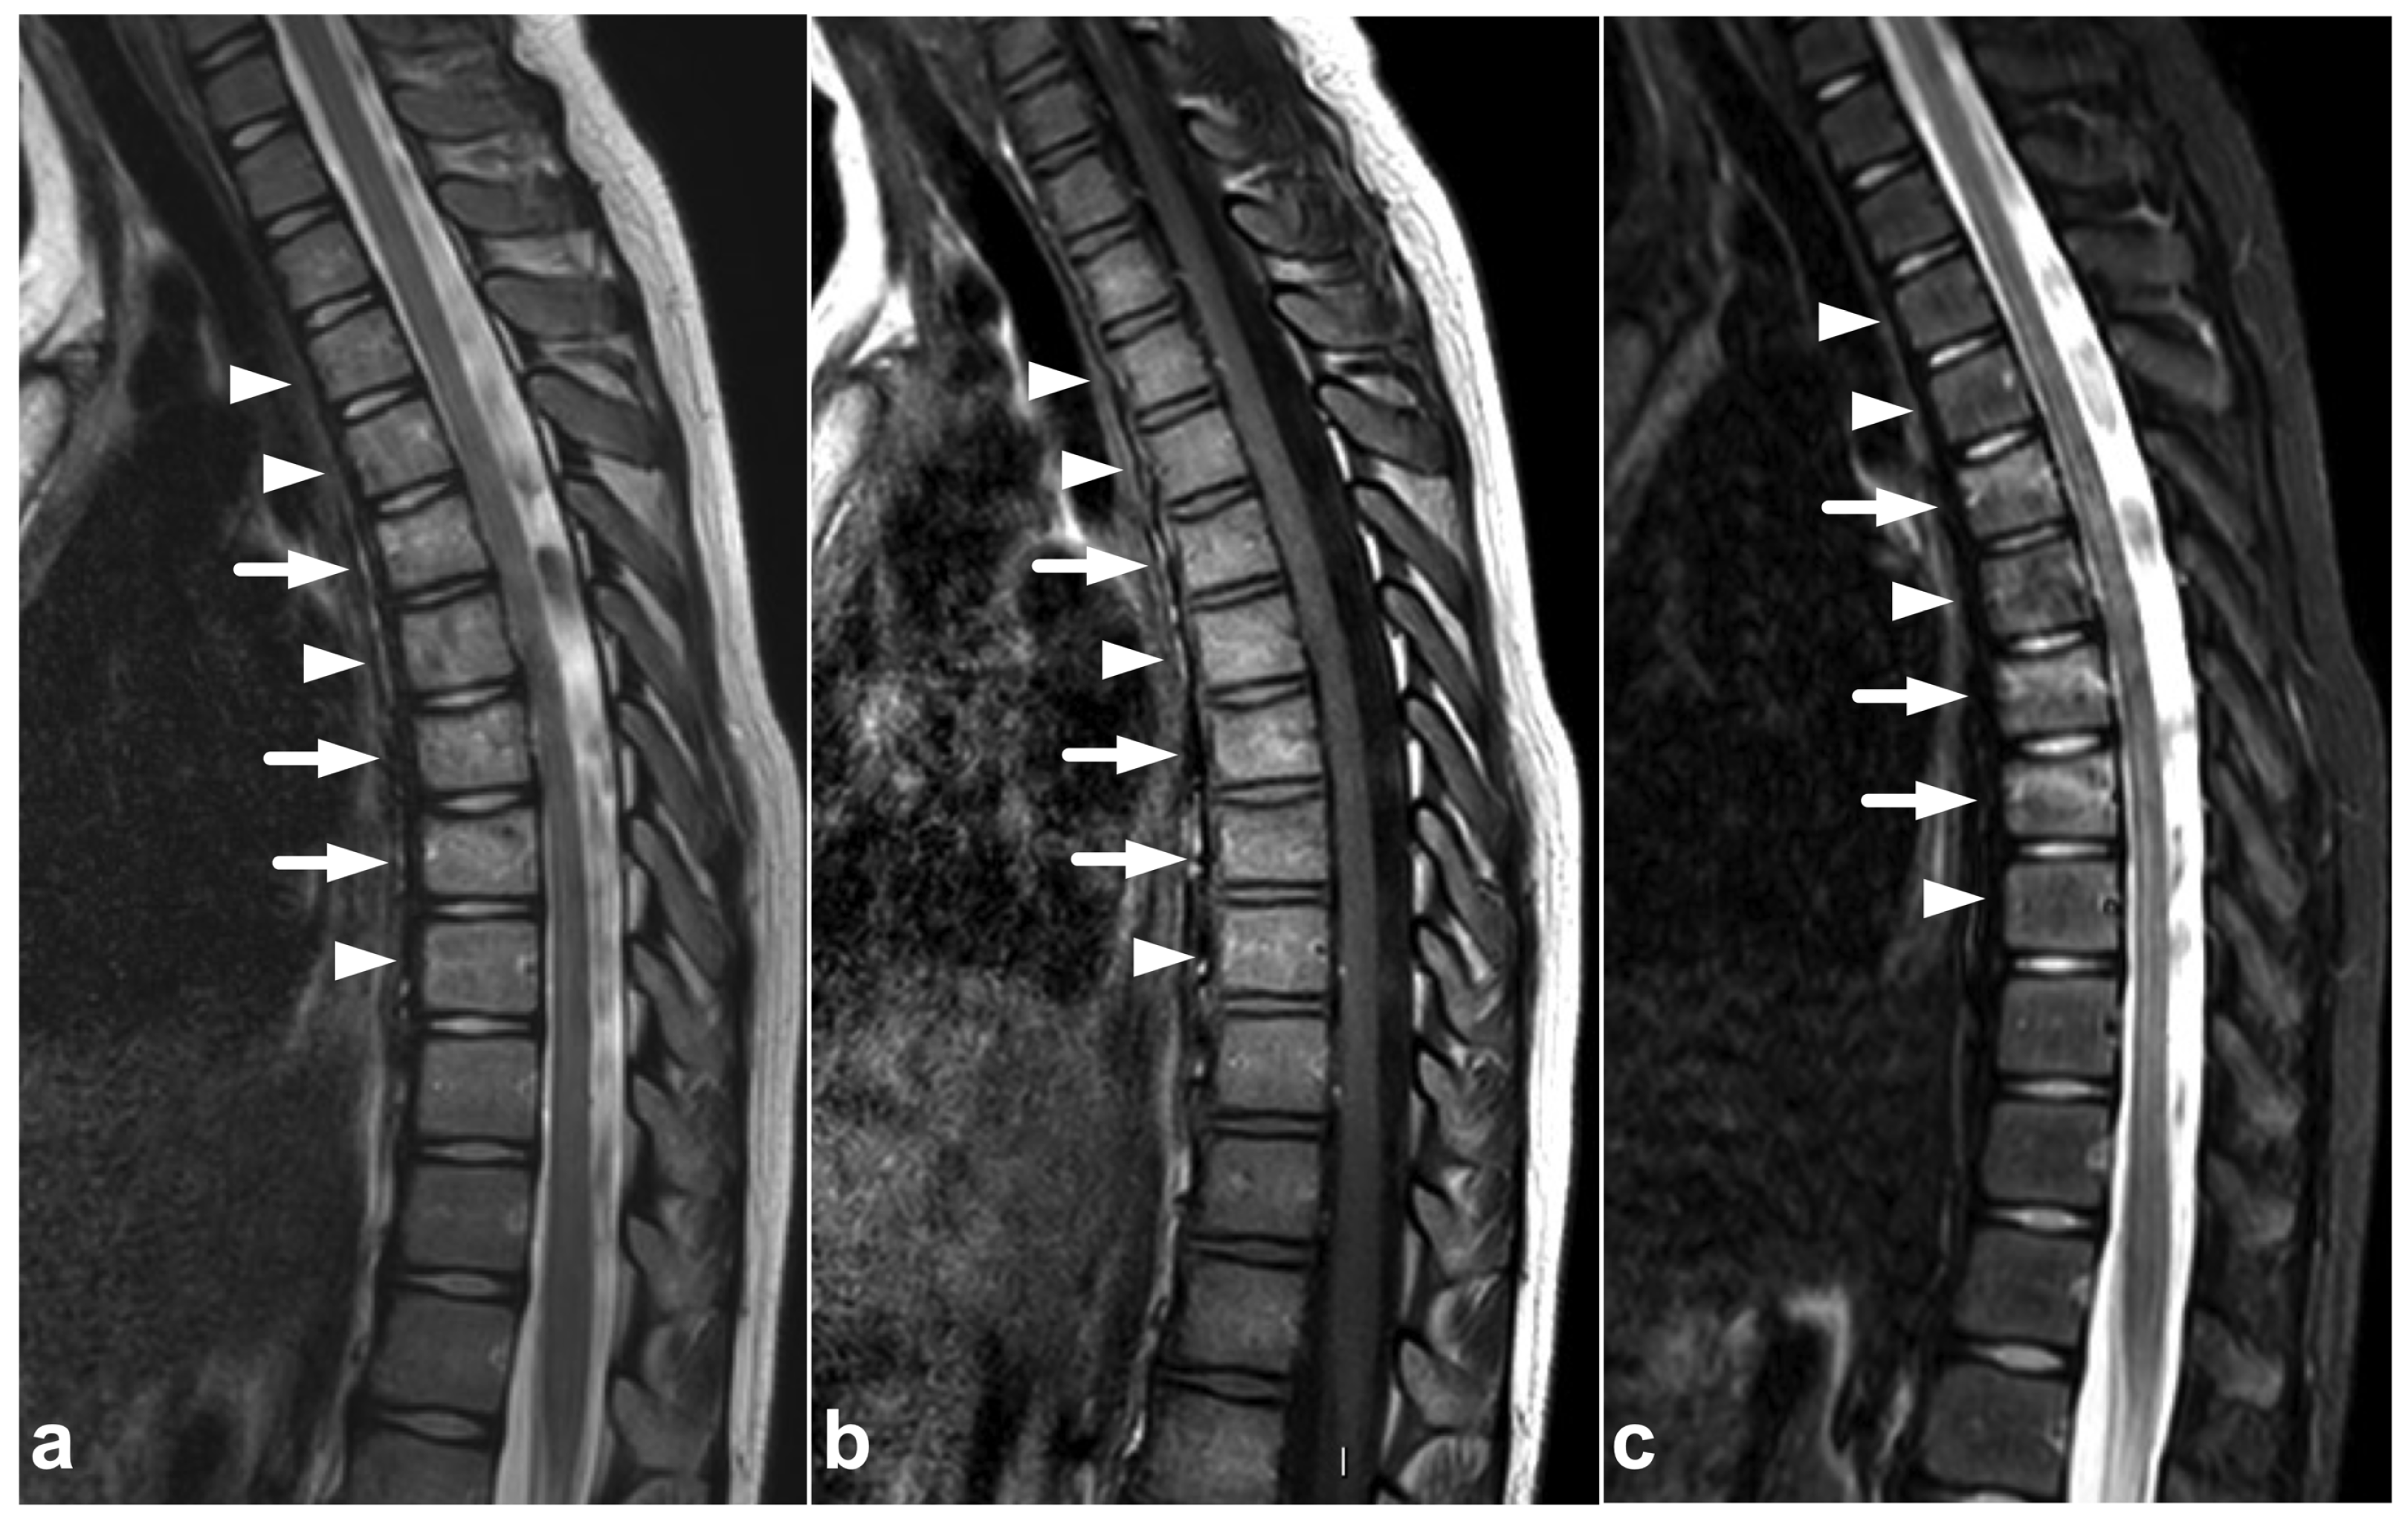

Figure 1.

(a) Sagittal T2-weighted. (b) Sagittal T1-weighted. (c) Sagittal STIR. A 9-year-old female, emergency MRI after a horseback riding accident. MRI demonstrates traumatic changes in vertebral bodies Th3–Th9, of which Th5, Th7, and Th8 have structural compressions (arrows). Th3, Th4, Th6, and Th9 have contusions without visible height loss (arrowheads).